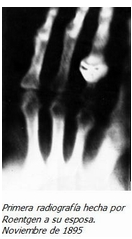

El 28 de diciembre de 1895, Willhem Conrad Roentgen durante 6 semanas estuvo encerrado en su laboratorio y decidió salir a mostrar su descubrimiento con la radiografía de mano de su esposa Anna Bertha ludwig y un mes más tarde hace la primera demostración ante la sociedad física de wurzburg